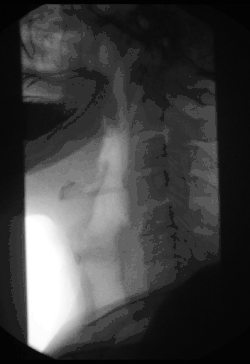

Gastrointestinal fluoroscopy

A barium swallow exam taken via fluoroscopy.

Fluoroscopy can be used to examine the digestive system using a substance that is opaque to X-rays (usually barium sulfate or gastrografin), which is introduced into the digestive system either by swallowing or as an enema. This is normally as part of a double-contrast technique, using positive and negative contrast. Barium sulfate coats the walls of the digestive tract (positive contrast), which allows the shape of the digestive tract to be outlined as white or clear on an X-ray. Air may then be introduced (negative contrast), which looks black on the film. The barium meal is an example of a contrast agent swallowed to examine the upper digestive tract. While soluble barium compounds are very toxic, the insoluble barium sulfate is nontoxic because its low solubility prevents the body from absorbing it. Investigations of the gastrointestinal tract include barium enemas, defecating proctograms, barium meals and swallows, and enteroclysis.[8]